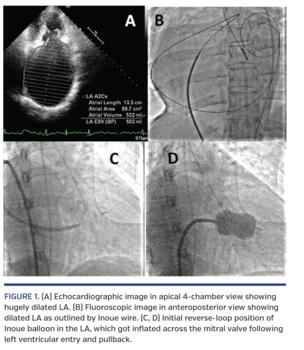

A 34-year-old man with chronic rheumatic heart disease, severe mitral stenosis, atrial fibrillation, and New York Heart Association class III was referred for percutaneous transvenous mitral commissurotomy (PTMC) in January 2016. In the past 5 years, he underwent 2 PTMC attempts at another institute; both attempts failed because the operator was unable to cross the mitral valve with the balloon. Two-dimensional echocardiography revealed mitral valve area of 0.8 cm2, transmitral diastolic gradient of 26/14 mm Hg, and no mitral regurgitation. The left atrium (LA) was hugely enlarged, with dimensions of 10.9 x 13.3 cm, area of 89.7 cm2, and volume of 502 mL in apical 4-chamber view (Figure 1A).

Following standard transseptal puncture, an Inoue balloon was positioned in the LA. A marked distance between the tip of a Mullen’s sheath at the interatrial septum and a pigtail catheter in the ascending aorta, as well as a large loop of Inoue wire outlining the LA boundary, were suggestive of huge LA (Figure 1B). The conventional method of direct vertical balloon entry across the mitral valve was not successful despite repeated attempts. Later, a reverse-loop (or double-loop) balloon was made by pushing the extra shaft length in the LA (Figure 1C). As the balloon tip reached near the mitral valve, the stylet was withdrawn 1-2 cm within the assembly and the balloon catheter was pushed into the left ventricle. Then, the distal half of the balloon was inflated and the entire assembly was pulled back until it got stuck at mitral valve. At this point, the remaining half of the balloon was inflated for mitral valve dilation (Figure 1D; Video 1). Post PTMC, the mitral valve area was 1.6 cm2. The patient remained relatively asymptomatic over 3 years of follow-up.